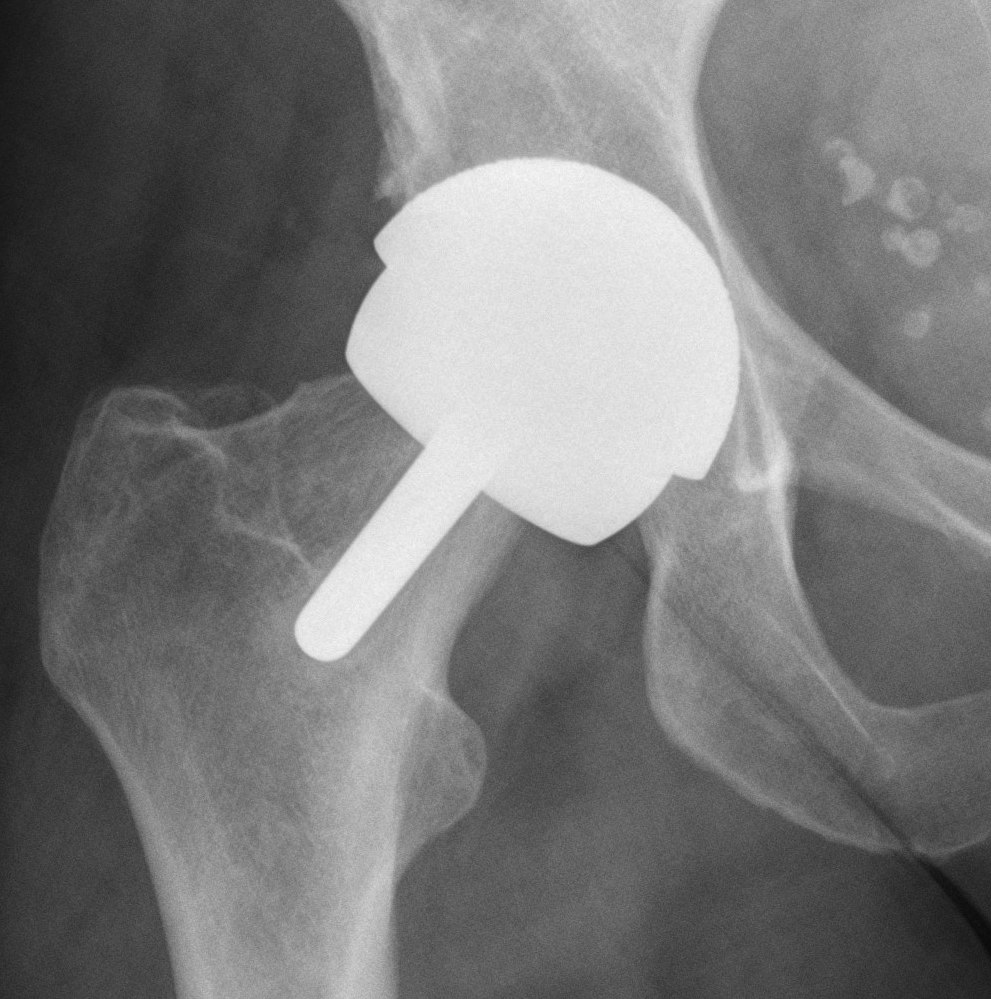

Hip Arthroscopy

Indications

Labral tear

Cam / pincer impingement

Loose bodies / trauma / synovial proliferation